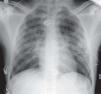

Case reportA 21-year-old man, black, a football player, was admitted via the emergency department with a clinical and laboratory diagnosis suggestive of acute appendicitis. There was no relevant family or personal history. Physical examination showed no abnormalities other than in the abdominal region. He underwent laparoscopic appendectomy under balanced general anesthesia, both of which were uneventful. The patient was extubated at the end of the procedure following reversal of neuromuscular blockade. Immediately after extubation, he developed a setting of respiratory distress, with abundant pink frothy sputum and significant arterial desaturation. Physical examination and chest X-ray revealed the presence of APE (Figure 1). After orotracheal reintubation and connection to a ventilator, the patient was transferred to our unit. Following treatment including high-flow oxygen therapy and administration of intravenous boluses of furosemide and isosorbide dinitrate, he showed rapid improvement and was extubated around four hours later (Figure 2). Other laboratory tests, together with electrocardiographic and echocardiographic assessment (Figures 3 and 4) excluded heart disease. There were no further complications.